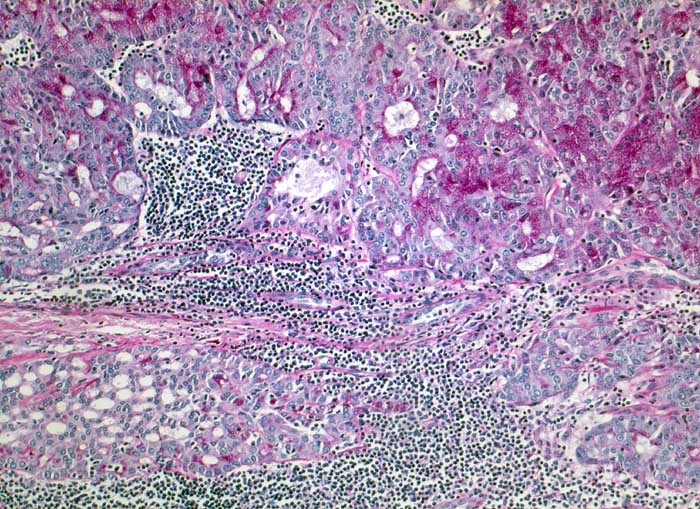

PathoPic – image database / PathoPic ID 5369 - Azinuszellkarzinom der Parotis

Azinuszellkarzinom der Parotis

Tumorzellen fokal Amylase und Diastase-PAS positiv

Azinuszellkarzinome sind nach den Mucoepidermoidkarzinomen und den nicht näher spezifizierten Adenokarzinomen die häufigsten malignen Speicheldrüsentumoren und am häufigsten bilateral (3%).

Azinär differenzierte Zellen können oft nur eine Minderheit ausmachen. Daneben gibt es auch kubische Zellen vom Streifstücktyp oder Zellen eines Adenokarzinoms ohne spezielle Differenzierung. Azinuszellkarzinome können viele Wachstumsmuster zeigen: mikrozystisch, solide, follikulär, papillär zystisch, glandulär. Typisch, aber nicht spezifisch ist ein ausgeprägtes lymphoides Stroma (keine echten Lymphknoten), welches zur richtigen Diagnose führen kann. Die Azinuszellen enthalten Diastase PAS positives Material und sind immunhistochemisch positiv für Amylase (oft nur herdförmig).

Histologie

Vergrösserung